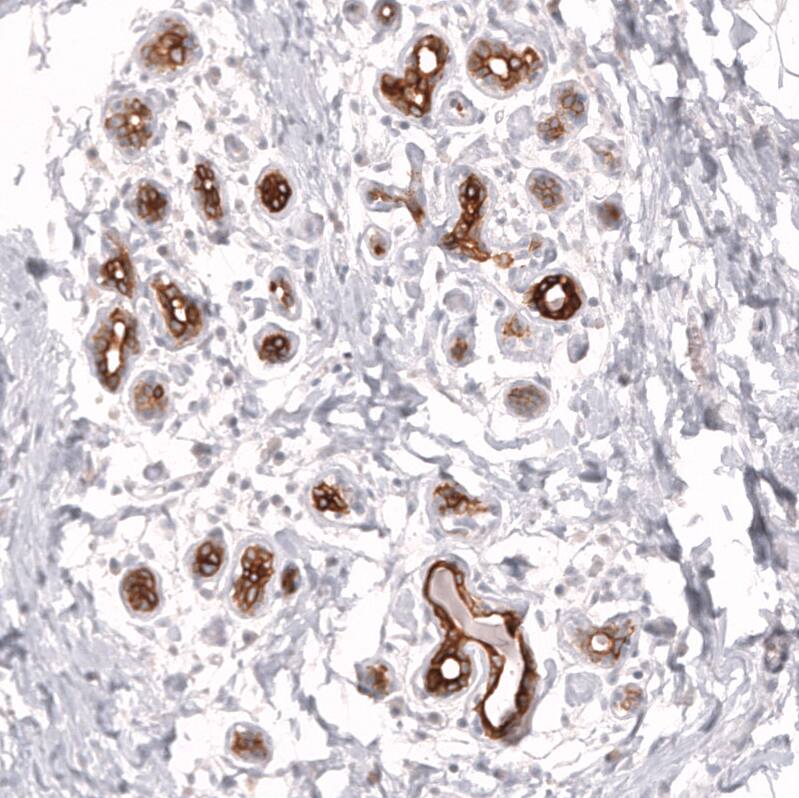

Staining of human breast shows strong membranous positivity in glandular cells.